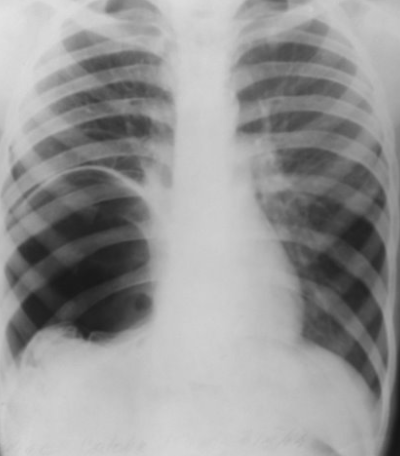

Rx toracică, incidență P-A

DESCRIERE:

DX: emfizem pulmonar

DD: